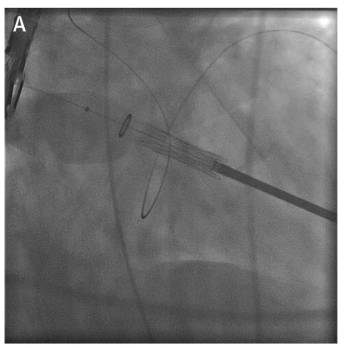

球囊扩张/闭式分离

TAVR/TMVR